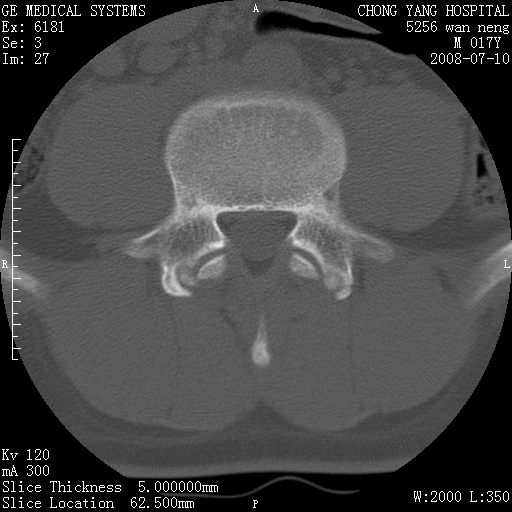

腰3、4椎弓崩裂

腰3、4椎弓不连

支持:腰3、4椎弓峡部崩裂。

腰3、4椎弓峡部不连

支持:腰3、4椎弓峡部崩解。

腰3、4,如受过外伤则为陈旧骨折,否则为骨质不连

图片漂亮,目前也只能看到腰3、4骨质不连

腰3、4椎弓峡部裂。

腰3、4椎弓峡部裂。支持

重建图像见多个椎弓峡部不连(不足为据),平扫未见异常。

支持腰3、4椎弓峡部崩裂。